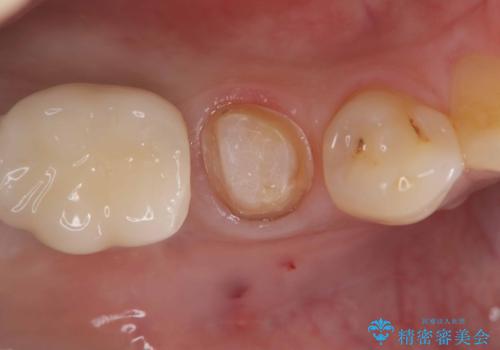

- 「食事をしていたら歯が欠けた」を主訴に来院された患者様です。

メタルインレーが入っており、インレーとの境の歯質が欠けている状態でした。

不幸中の幸いで欠けているところが根っこよりも上だったため、オールセラミッククラウンで治療を行いました。

銀歯を除去後、やはり銀歯の下は虫歯になっていましたので、虫歯を除去した後にオールセラミッククラウンで被せました。